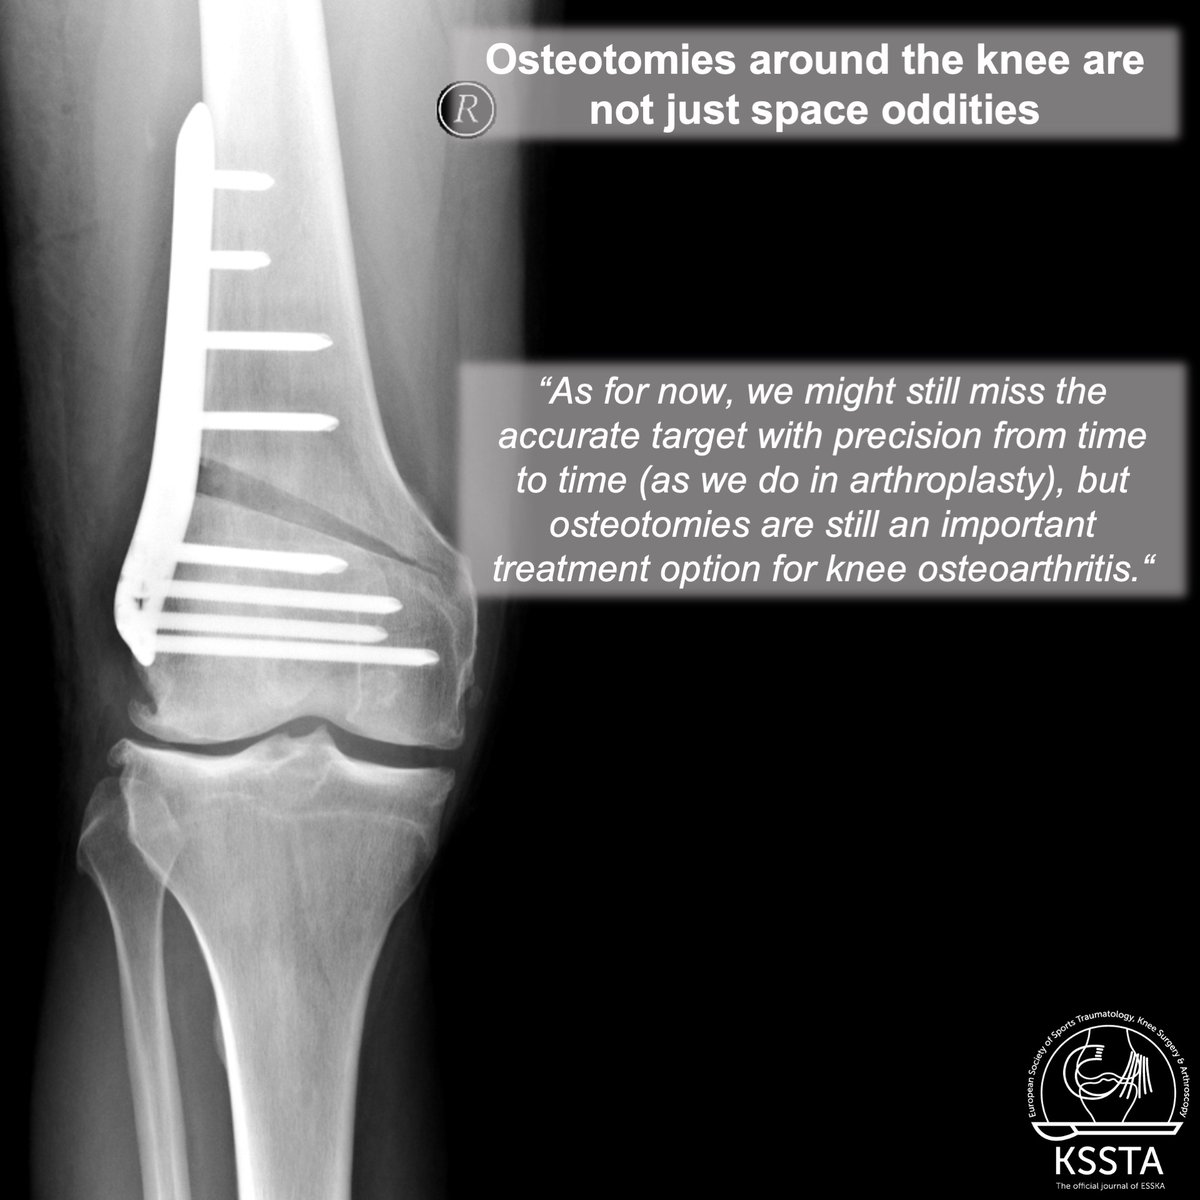

Have you read the latest KSSTA Editorial on the "Comeback of Osteotomies around the knee"? Reach here:

https://t.co/pppf2yly3A Read more about the comeback of osteotomies around the knee in this editorial published in the October issue of KSSTA. #osteotomy #osteoarthritis #knee #alignment #orthopaedic